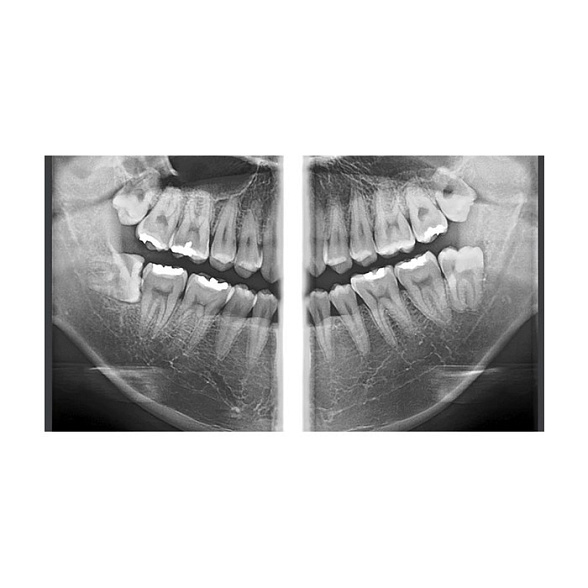

Панорамные режимы (2D):

- Стандартная ортопантомограмма (ОПТГ) для общей оценки состояния зубных рядов, костной ткани и суставов.

- Режимы для детей с уменьшенной дозой облучения.

- Снимки височно-нижнечелюстных суставов (ВНЧС) в открытом и закрытом положении.

- Снимки верхнечелюстных пазух (синус-снимки).

- Высокая детализация изображений: Получайте четкие и контрастные снимки с минимальным уровнем шумов. Это критически важно для оценки анатомии каналов, обнаружения скрытых патологий, планирования имплантации и эндодонтического лечения.